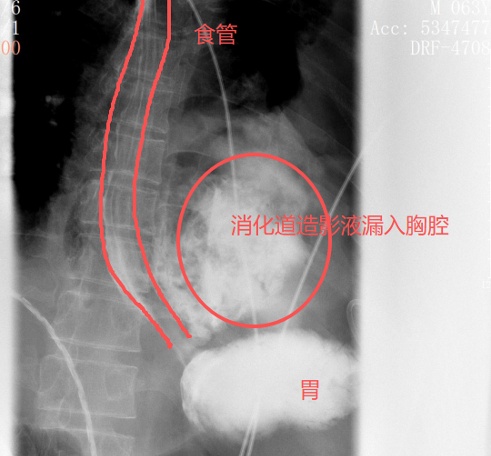

转院时,患者病因成谜。在晨会交班时,胸外科主任刘继先敏锐地捕捉到一个关键细节,他多问了一句:“这个病人,发病前有没有呕吐?”“有!吃完包子之后吐了两次,吐完就开始痛了。”在得到肯定答复后,刘主任立即警觉,判断这可能是一种极为凶险的疾病——“自发性食管破裂”(Boerhaave综合征),并紧急安排了口服钡餐检查。

结果证实了他的判断:

钡剂从食道下段的裂口处

大量漏入了左侧胸腔